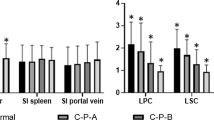

Hepatocellular uptake index

Average SI of the spleen in the HBP was 197 ± 36.4 before PVE, 201 ± 30.8 14 days after PVE and 205 ± 29.8 28 days after PVE. HUI of the LLL increased steadily after PVE and was significantly higher at both 14 and 28 days after PVE compared to pre PVE (P < 0.05). HUI of the residual liver after surgery was lower than after PVE but this was not statistically significant. HUI of the RLL was significantly lower both 14 days and 28 days after PVE compared to baseline before PVE (P < 0.05), but did not decrease significantly from 14 days to 28 days after PVE (Fig. 6). Serum bilirubin correlated negatively with HUI of LLL (r 2 = −0.535; P < 0.05) but not for RLL (r 2 = −0.306; P = 0.065). Patient age correlated negatively with HUI of the RLL before PVE (r 2 = −0.530; P < 0.05), HUI of the RLL 14 days after PVE (r 2 = −0.624; P < 0.05), HUI of the LLL 14 days after PVE (r 2 = −0.455; P < 0.05) and HUI 10 days post surgery (r 2 = −0.500; P < 0.05).